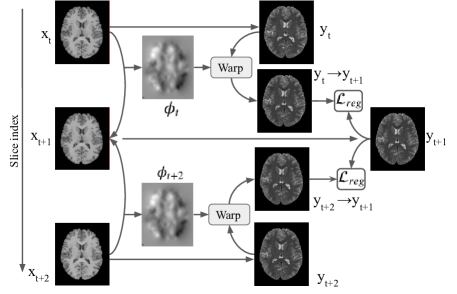

To obtain the displacement between consecutive slices, we use an unsupervised registration network [1] to learn a deformation field of a slice and its consecutive slices . The deformation field can be obtained using a convolutional neural network (CNN) [1] by minimizing the loss function

where denotes the spatial transformation operation. The first term ensures that the distance between the next slice and the warped current slice to be close. The second term imposes regularization on .

To guarantee the consistency of the image translation, the loss is used to measure the difference between the warping of fake images on consecutive slice and the translation of reference slice . We define the temporal consistency loss function for mapping and as:

Fig. 2 illustrates an example for image-to-image translation from domain using temporal constraints. Let be consecutive slices of real images in the source domain . A mapping function generates the fake image on target domain . On the source domain, we can learn displacement fields between and . To constrain the consistency of the mapping from , we minimize the distance (i) between the warped fake image and for mapping from slice and slice, and (ii) between the warped fake image and for mapping from slice and slice.